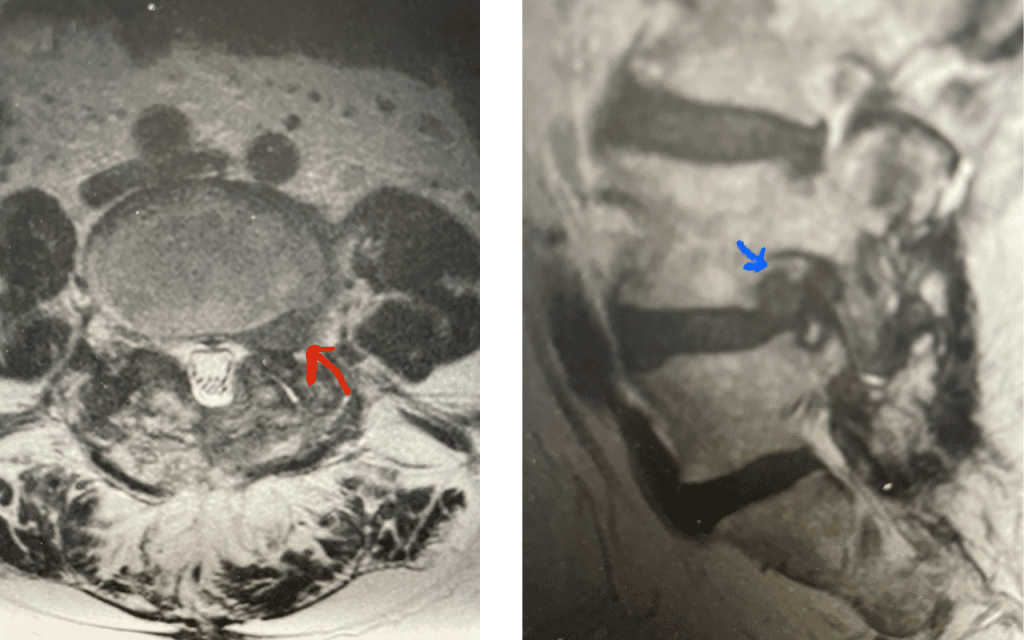

Fig 9: Axial and Sagittal T2-weighted lumbar MRI demonstrating left L4-5 far lateral disc herniation (red arrow). Notice how on the sagittal MRI the disc herniation fills the foramen and is superiorly oriented, compressing the left L4 nerve root against the L4 pedicle (blue arrow).